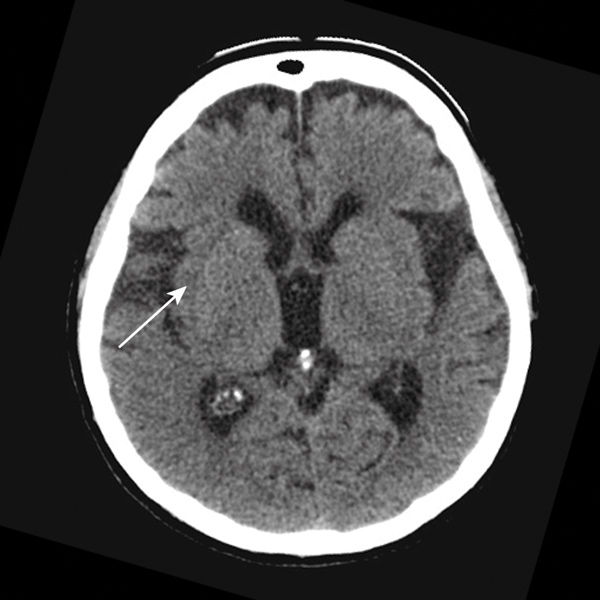

The local hospital acute stroke treatment protocol was followed, commencing with attendance by a code stroke team. Conventional non-contrast computed tomography (CT) of the brain performed 2 hours after symptom onset showed subtle and early obscuration of the right posterior insular cortex (Box 1). Findings on perfusion CT (Aquilion One, Toshiba Medical Systems, Otawara, Japan) were consistent with a large area of ischaemic penumbra in a right posterior middle cerebral artery (MCA) distribution (Box 2), corresponding to a right MCA (M2 segment) thrombotic occlusion on CT angiography.